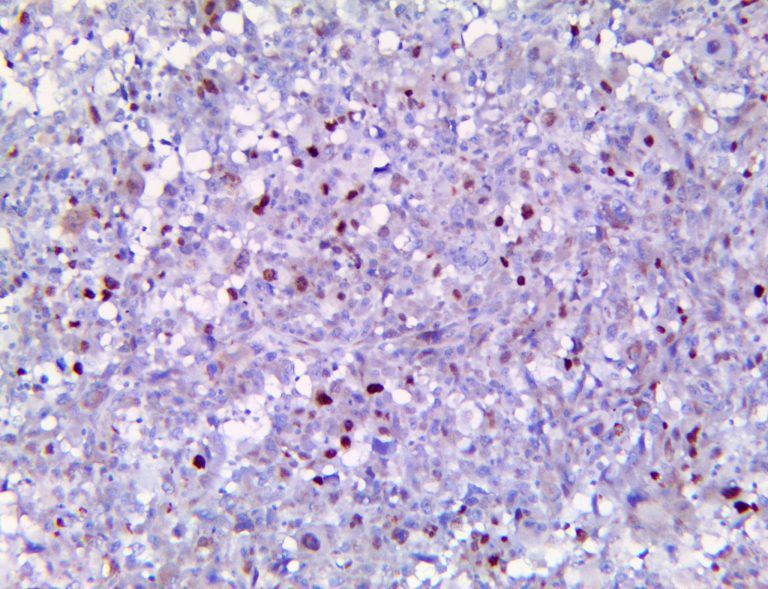

It is the ICU physician who is most likely to witness one of the deadliest manifestations of the abnormal immunological response, the cytokine storm syndrome (CSS). This response is also referred to by some as the cytokine release syndrome (CRS). CSS is characterized by continuous activation and expansion of macrophage and lymphocyte populations, which secrete large amounts of cytokines, causing the cytokine storm. This massive cytokine release is akin to hemophagocytic lymphohistiocytosis (HLH) disease, a syndrome characterized by initial unchecked and persistent activation of cytotoxic T lymphocytes and NK cells.

Clinical and laboratory manifestations of HLH include fever, enlarged liver and/or spleen, neurologic dysfunction, coagulopathy, liver dysfunction, cytopenias (i.e., low levels of erythrocytes, leukocytes, and/or platelets), hypertriglyceridemia, hyperferritinemia, hemophagocytosis, and eventually diminished NK cell activity as the immune system becomes progressively paralyzed. HLH can be familial (primary HLH) or secondary to another disease process (sHLH), such as rheumatic disease, in which it is referred to as macrophage activation syndrome (MAS, characterized by elevated ferritin).

This activation induces inflammatory monocytes to highly express IL-6, starting a localized and then systemic cascade effect that results in hyperproduction of IL-6, which accelerates the inflammatory process. Because IL-6 also increases vascular permeability, excessive levels cause blood vessels to become very leaky. This, along with clotting factors released from vascular endothelial cells, stimulates the coagulation cascade, resulting in microthrombosis (tiny clots), which leads to ischemia and tissue death of the kidney, intestines, heart, liver, brain and extremities.